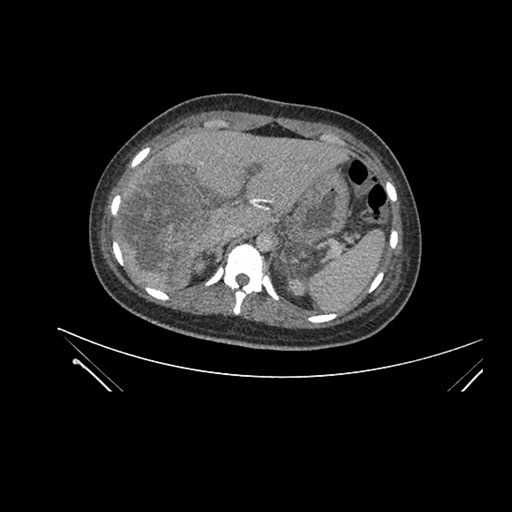

Imaging Analysis

Look through the patient's CT scan to identify any areas of concern for the necessary procedure.

Axial Arterial

Based on initial findings, which issue(s) would you be most concerned about?